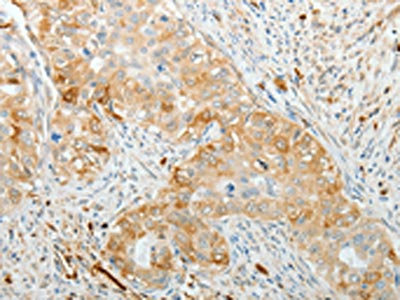

The image on the left is immunohistochemistry of paraffin-embedded Human cervical cancer tissue using CSB-PA116506(ADM Antibody) at dilution 1/20, on the right is treated with synthetic peptide. (Original magnification: ×200)